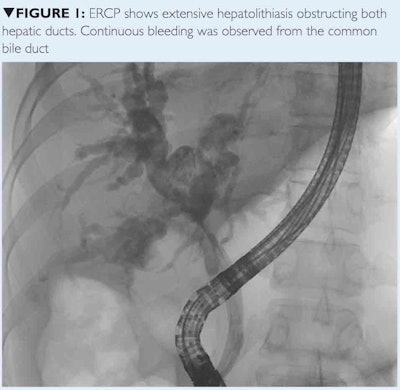

With appropriate shielding, a selective hepatic angiogram was performed that showed brisk active extravasation from the proximal right hepatic artery, just distal to the origin of the middle hepatic artery. The remaining arterial branches were unremarkable. Operative repair was deemed infeasible by the hepatobiliary surgeon. Therefore, transcatheter arterial embolization (TAE) was performed using Gelfoam and microcoils.